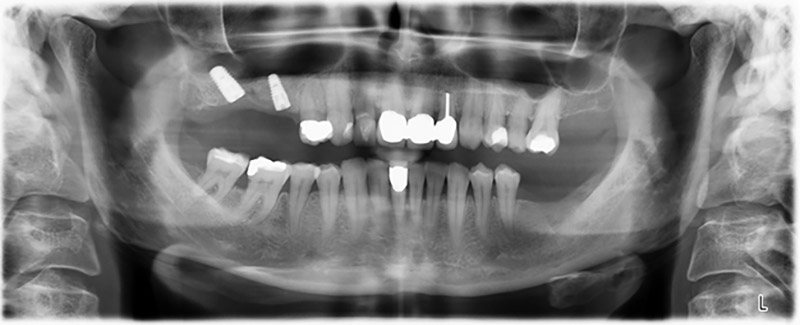

Шест месеца след екстракцията на зъби 16 и 14 се извършва преглед с дигитален томограф (DVT, Planmeca), с цел планиране и намаляване на възможните рискове. Ясно се вижда, че костта не се е регенерирала до желания обем (Фиг. 2 до 7).

Снимки 2 до 7: DVT със силно намален хоризонтален костен обем.